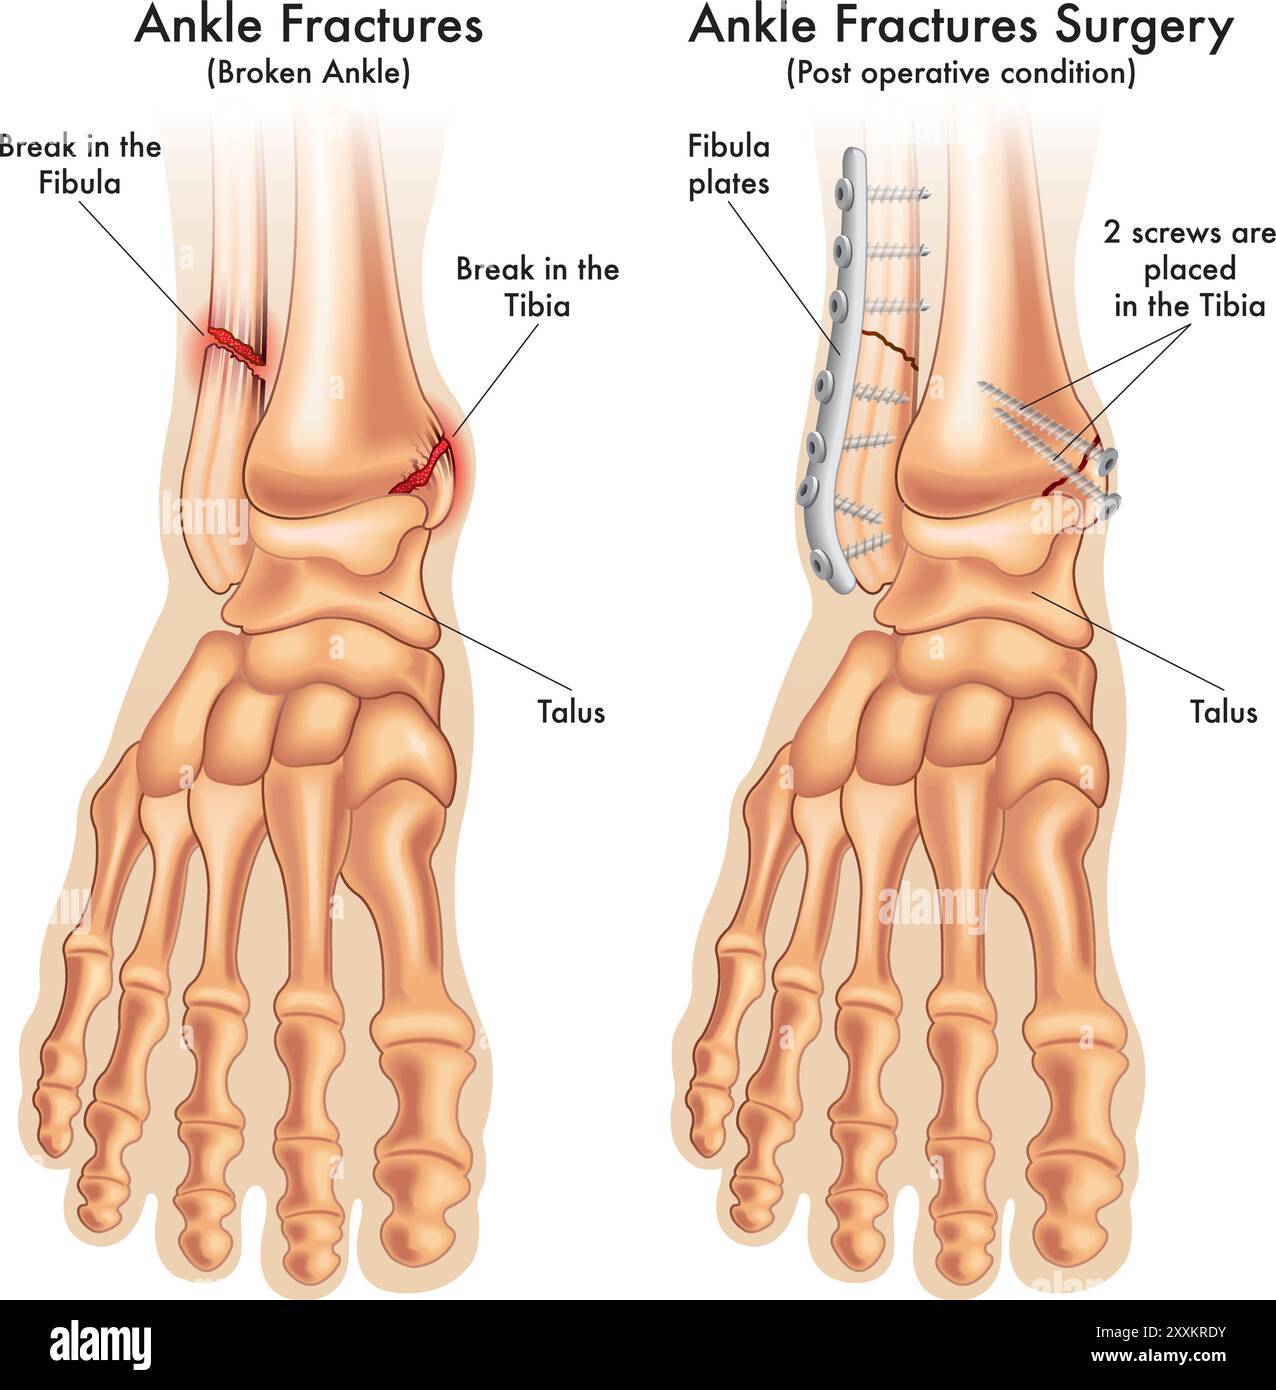

RF2XXKRDY–l'illustration médicale compare une cheville fracturée avant et après la chirurgie, avec des annotations.